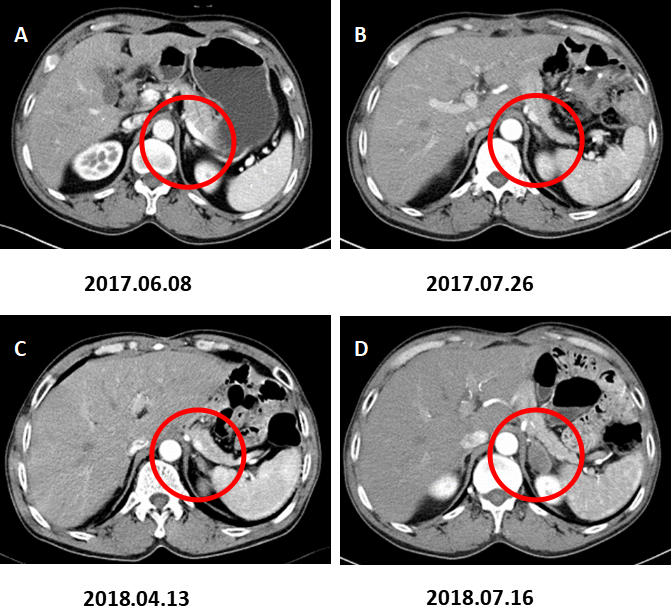

图4. 左肾上腺转移。

A:术前CT增强(2017.06.08)、B:术后CT增强(2017.07.26)、C:术后CT增强(2018.04.13)示左肾上腺增粗,增生考虑。D:术后CT增强复查(2018.07.16)示左肾上腺结节,约2.8×1.8cm,增强后不均匀强化,转移考虑。

图5. 腹膜后淋巴结转移。

A:术前CT增强(2017.06.08)B:术后CT增强(2017.07.26)、C:术后CT增强(2018.04.13)示腹膜后小淋巴结。D:术后CT增强复查(2018.07.16)示腹膜后多发肿大淋巴结,转移考虑。

图6. 肝脏多发转移。

术前CT增强A(2017.06.08),术后CT增强B(2017.07.26)、C(2018.04.13)未见肝脏转移。D:术后CT增强复查(2018.07.16)示肝脏多发转移灶。